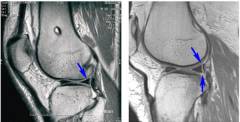

МРТ представляет собой высокоинформативный метод диагностики повреждений менисков. Метод основывается на явлении ядерно-магнитного резонанса. Данный метод позволяет измерить электромагнитный отклик ядер на их возбуждение определенной комбинацией электромагнитных волн в постоянном магнитном поле высокой напряженности. Точность этого метода в диагностике повреждений мениска составляет до 90 – 95%. Для проведения исследования обычно не требуется специальной подготовки. Непосредственно перед проведением МРТ обследуемый должен снять все металлические предметы (очки, ювелирные изделия и др.). Во время исследования пациент должен лежать ровно, не двигаться. Если пациент страдает нервозностью, клаустрофобией, то предварительно ему дадут успокоительный препарат.

Классификация степени изменения менисков, визуализируемых на МРТ (по Stoller):

- нормальный мениск (без изменений);

- появление в толще мениска очагового сигнала повышенной интенсивности, который не достигает поверхности мениска;

- появление в толще мениска литейного сигнала повышенной интенсивности, который не достигает поверхности мениска;

- появление сигнала повышенной интенсивности, который достигает поверхности мениска.

Истинным разрывом мениска считают только изменения третьей степени. Третью степень изменений также можно условно разделить на степень 3-а и 3-б. Степень 3-а характеризуется тем, что разрыв распространяется только до одного края суставной поверхности мениска, а для степени 3-б характерно распространение разрыва до обоих краев мениска.

Также установить диагноз повреждения мениска можно по форме мениска. На снимках в норме в вертикальной плоскости мениск имеет форму, которая напоминает бабочку. Изменение формы мениска может служить признаком его повреждения.

Признаком повреждения мениска может также служить симптом «третей крестообразной связки». Появление данного симптома объясняется тем, что в результате смещения мениск оказывается в межмыщелковой ямке бедренной кости и практически прилегает к задней крестообразной связке.